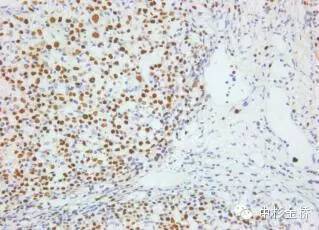

圖為EBER原位雜交染色DBA顯色,蘇木素復(fù)染